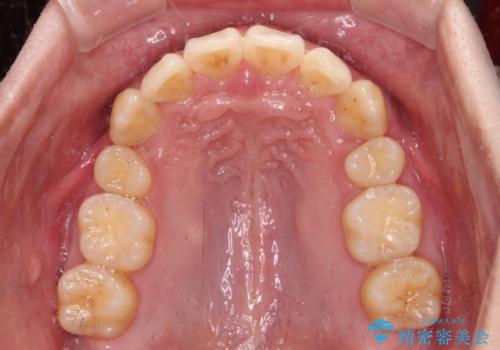

- 八重歯を気にして来院された患者様です。

顕著な上顎の八重歯とディープバイトであったため、上顎の左右第一小臼歯を抜歯することとしました。

犬歯歯根の位置や奥歯の咬み合わせから、ワイヤー装置での治療を強くおすすめいたしましたが、ご本人の強い希望により、妥協的な仕上がりとなることを了解いただき、インビザラインにて矯正治療を行うこととしました。

インビザライン単体で、左右ともに移動の難しい位置に歯根のある犬歯を整えるのは困難と判断し、補助装置を併用することとしました。